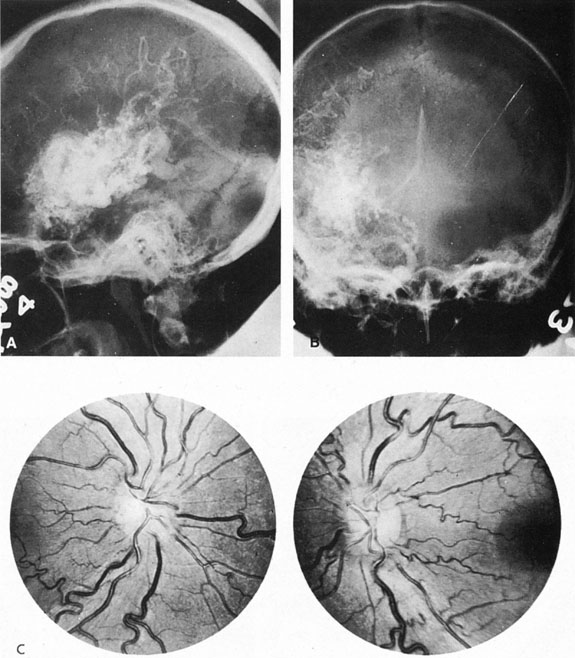

From 85% to 90% of AVMs are in the supratentorial compartment and are supplied primarily by the carotid circulation (Figs. 7 and 8). The remainder are supplied by the vertebrobasilar system. The approximate frequency of location is as follows: frontal, 22%; temporal, 18%; parietal, 27%; occipital, 5%; and deep intraventricular or paraventricular, 18%. The intracerebral site of the malformation does not necessarily indicate that there will be signs referable to that area simply from the mass effect of the malformation. Clinical features primarily result from subarachnoid hemorrhage or intraparenchymal hemorrhage with hematoma formation.

Fig. 7. Supratentorial arteriovenous malformation in a 28-year-old woman with a history of focal motor seizures for many years and a recent subarachnoid hemorrhage. A: Lateral projection carotid arteriogram demonstrating a huge deep hemispheral arteriovenous malformation. B: Frontal projection. C: Fundus photograph showing anomalous tortuous vasculature in each eye. No retinal arteriovenous shunt was detectable.

Fig. 8. Multiple supratentorial arteriovenous malformations (AVMs). A: Lateral projection of left carotid arteriogram shows dilated afferent artery (solid arrow) feeding the right hemispheric parietal AVM (open arrow). B: Right carotid injection fills a second, more posteriorly located, parietooccipital AVM (open arrow), which drains immediately to markedly dilated cortical veins (curved arrow).

In general, when hemorrhage occurs involving a portion of the visual radiations, a homonymous visual field defect is to be expected. Selective involvement of the anterior visual pathways may occur either with extensive venous angiomas at the base of the brain or as part of the Wyburn-Mason syndrome (see later), with direct involvement of the optic nerve, chiasm, or tract. Other variants such as congenital cavernous hemangiomas may involve the anterior visual pathways,68 as may intraparenchymal cryptic AVMs69 and present as symptomatic visual loss also resulting from hemorrhage and hematoma. Amaurosis fugax may even be the presenting symptom of supratentorial AVMs when blood is shunted to the meningeal circulation from the ophthalmic artery.70 When supratentorial AVMs drain into dural venous sinuses or the vein of Galen, distant ocular effects evolve, such as proptosis71 or ophthalmoplegia72 because of arterialization of cavernous sinus complex.

Of particular interest are those AVMs that involve the occipital lobe (Fig. 9). The clinical differentiation of migraine from a cerebral AVM was previously regarded as difficult because the clinical features of occipital lobe AVMs include visual phenomena or headaches. However, in most cases the clinical distinction is possible. In 26 cases with occipital AVM, two distinct syndromes were defined in 18 patients: occipital epilepsy and occipital apoplexy.73 Focal seizures with occipital malformations consist of elementary visual sensations similar to the phenomena evoked by direct cortical stimulations. When seizure activity occurs in the striate cortex (area 17), the patient usually reports sensations of moving lights in the right or left homonymous fields. The sensations are poorly formed, episodic, usually brief, sometimes colored, and unassociated with the angular, scintillating figures so characteristic of migrainous cortical phenomena. Epileptic discharges from areas 18 and 19 cause photopsias that are unlikely to remain stationary and to flicker rapidly. The epileptic photopsias usually last only seconds; occasionally they last for a few minutes before the onset of a generalized seizure. In other instances only the brief visual episodes occur without spreading to produce a generalized seizure. Momentary dimming or blindness in one or both homonymous fields may be experienced with seizure activity in the occipital areas.

Fig. 9. Carotid arteriogram of an occipital lobe arteriovenous malformation (AVM). Lateral (A) and frontal (B) projections demonstrating a small occipital AVM (arrow). The patient was a 23-year-old woman who presented with severe apoplectic unilateral headache, total left homonymous hemianopia, and mild nuchal rigidity. Despite xanthochromic cerebrospinal fluid, she was initially diagnosed elsewhere as having migraine. An AVM was successfully resected, and a small occipital lobe hematoma was removed.